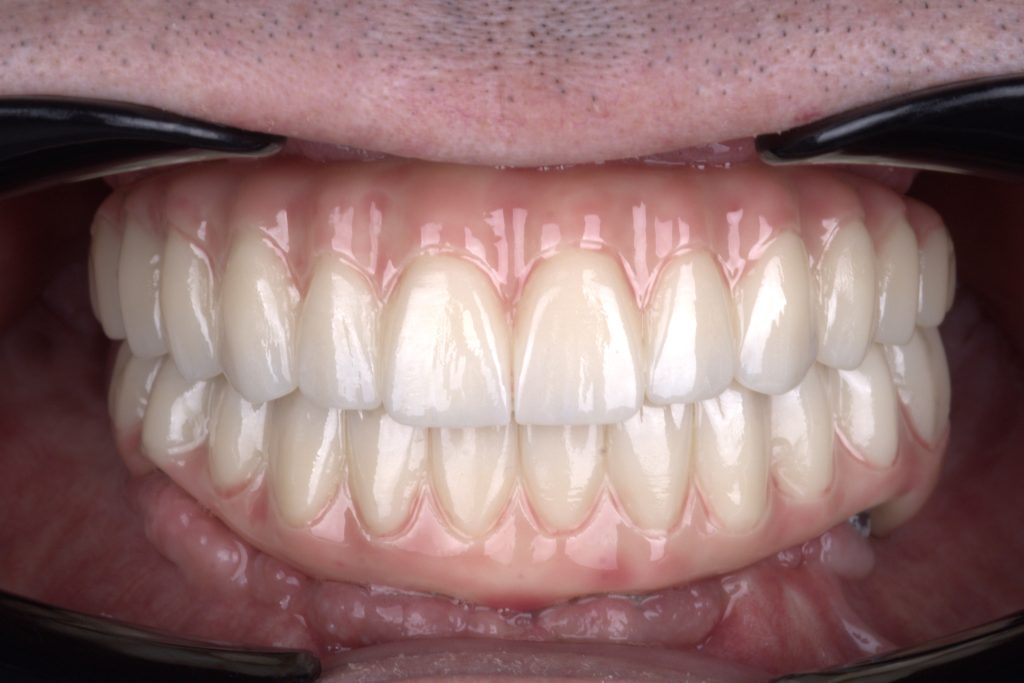

Final monolithic zirconia restoration for a double All-on-4 case study.

Finally a deserved smile Beautiful teeth

Precision-engineered occlusion, expertly crafted by our lab at White Clinic Belgrade.

Easy transition from proper provisional teeth to final ceramic restoration

The beauty of precision: Capturing the perfect bite in monolithic zirconia.

Exceptional monolithic zirconia expertly crafted by our laboratory team at White Clinic Belgrade

Visual satisfaction: The seamless occlusion of monolithic zirconia at White Clinic Belgrade.

The beauty of precision Capturing the perfect bite in full contour zirconia

Exquisite incisal edges and perfect occlusion in full-contour zirconia.

I just cant resist a closer look at these exquisite incisal edges